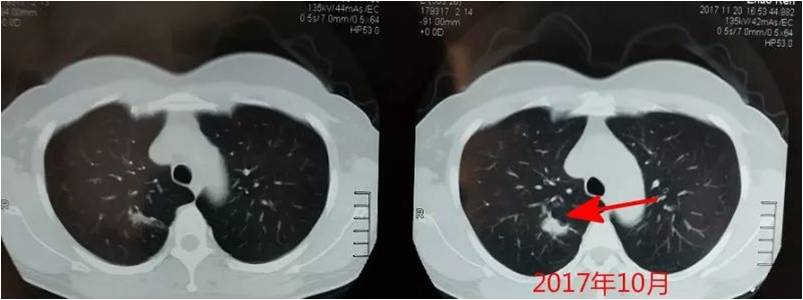

下面這張圖是患者初次發現結節時的CT圖: